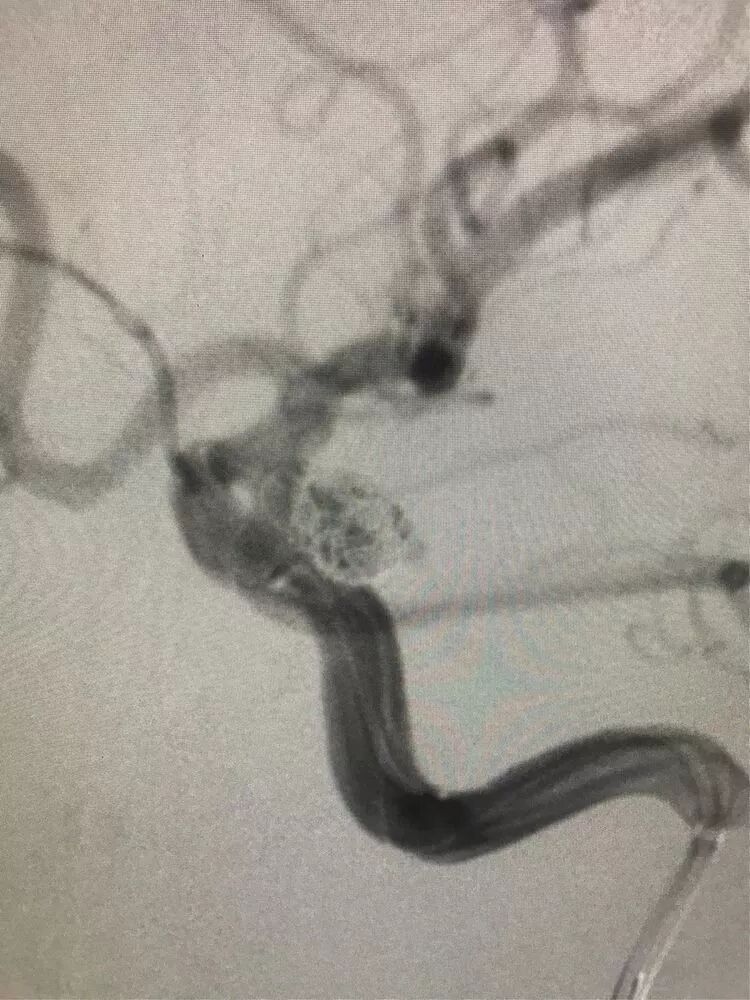

女,73岁,蛛网膜下腔出血量还挺多的,H-H 分级4级

造影显示左侧后交通动脉瘤

椎动脉造影没发现大脑后动脉,双侧的大脑后动脉都是由颈内动脉-后交通动脉发出,双侧胚胎型大脑后动脉

我们来看看动脉瘤的结构:红色为颈内动脉走向,绿色为后交通动脉走向,蓝色为动脉瘤

栓塞的要点,既要致密填塞,又要保证颈内动脉和后交通动脉的通畅。决定通过对侧前交通动脉-颈内动脉远端-后交通动脉途径来置入输送支架的微导管,从后交通动脉释放支架直到颈内动脉末端,以达到一个支架对颈内动脉和后交通动脉的保护